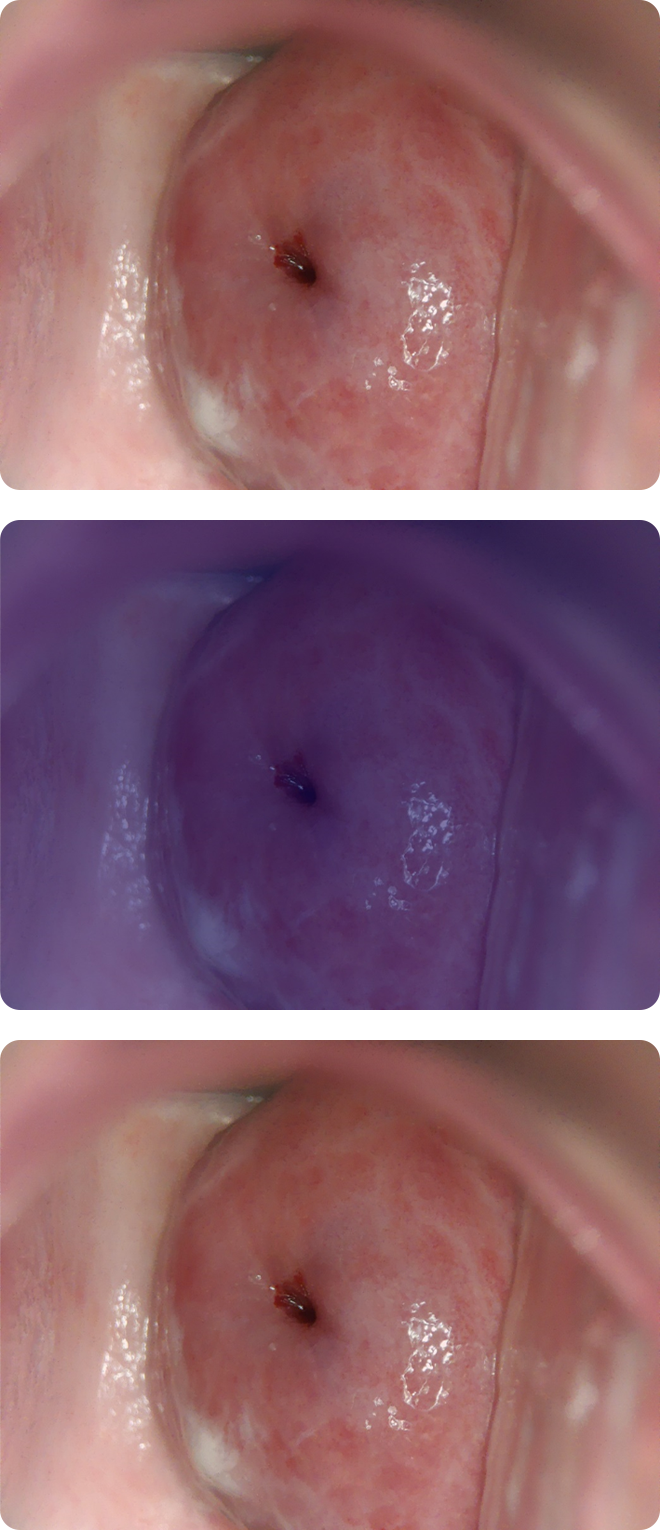

Cerviray AI

Normal

CIN1

CIN2-3

CIN3+